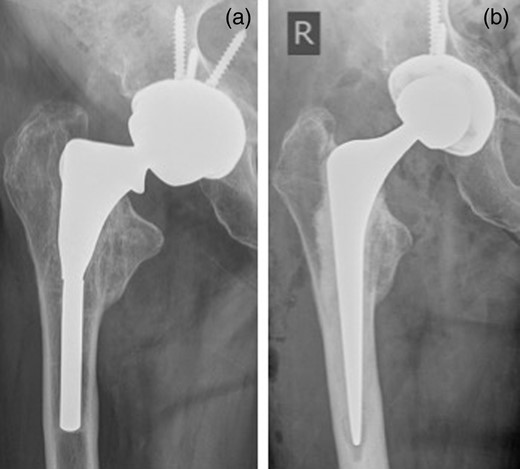

A 74-year-old man presented to our MoM surveillance clinic with sudden onset of severe left hip pain. Five years prior to presentation, he had undergone a left MoM THR with a Profemur stem and Procotyl cup (Wright Medical Ltd, UK). The patient also had undergone a right THR with a similar prosthesis 6 years prior to this presentation. One year prior to presentation, he was noticed to have raised metal ions (cobalt and chromium) and X-ray of his left hip showed radiolucent lines in Zones 1 and 7. While awaiting an MRI scan, he contacted our clinic complaining of sudden severe left hip pain without history of trauma. X-ray of his left hip showed a distal stem fracture (Fig. 1a). He was admitted from the clinic and his left hip was revised with ceramic on polyethylene bearing using Exeter stem and Trident cup (Stryker UK Limited; Fig. 1b).

(a) Distal stem fracture of left hip prosthesis. (b) Post-revision X-ray.